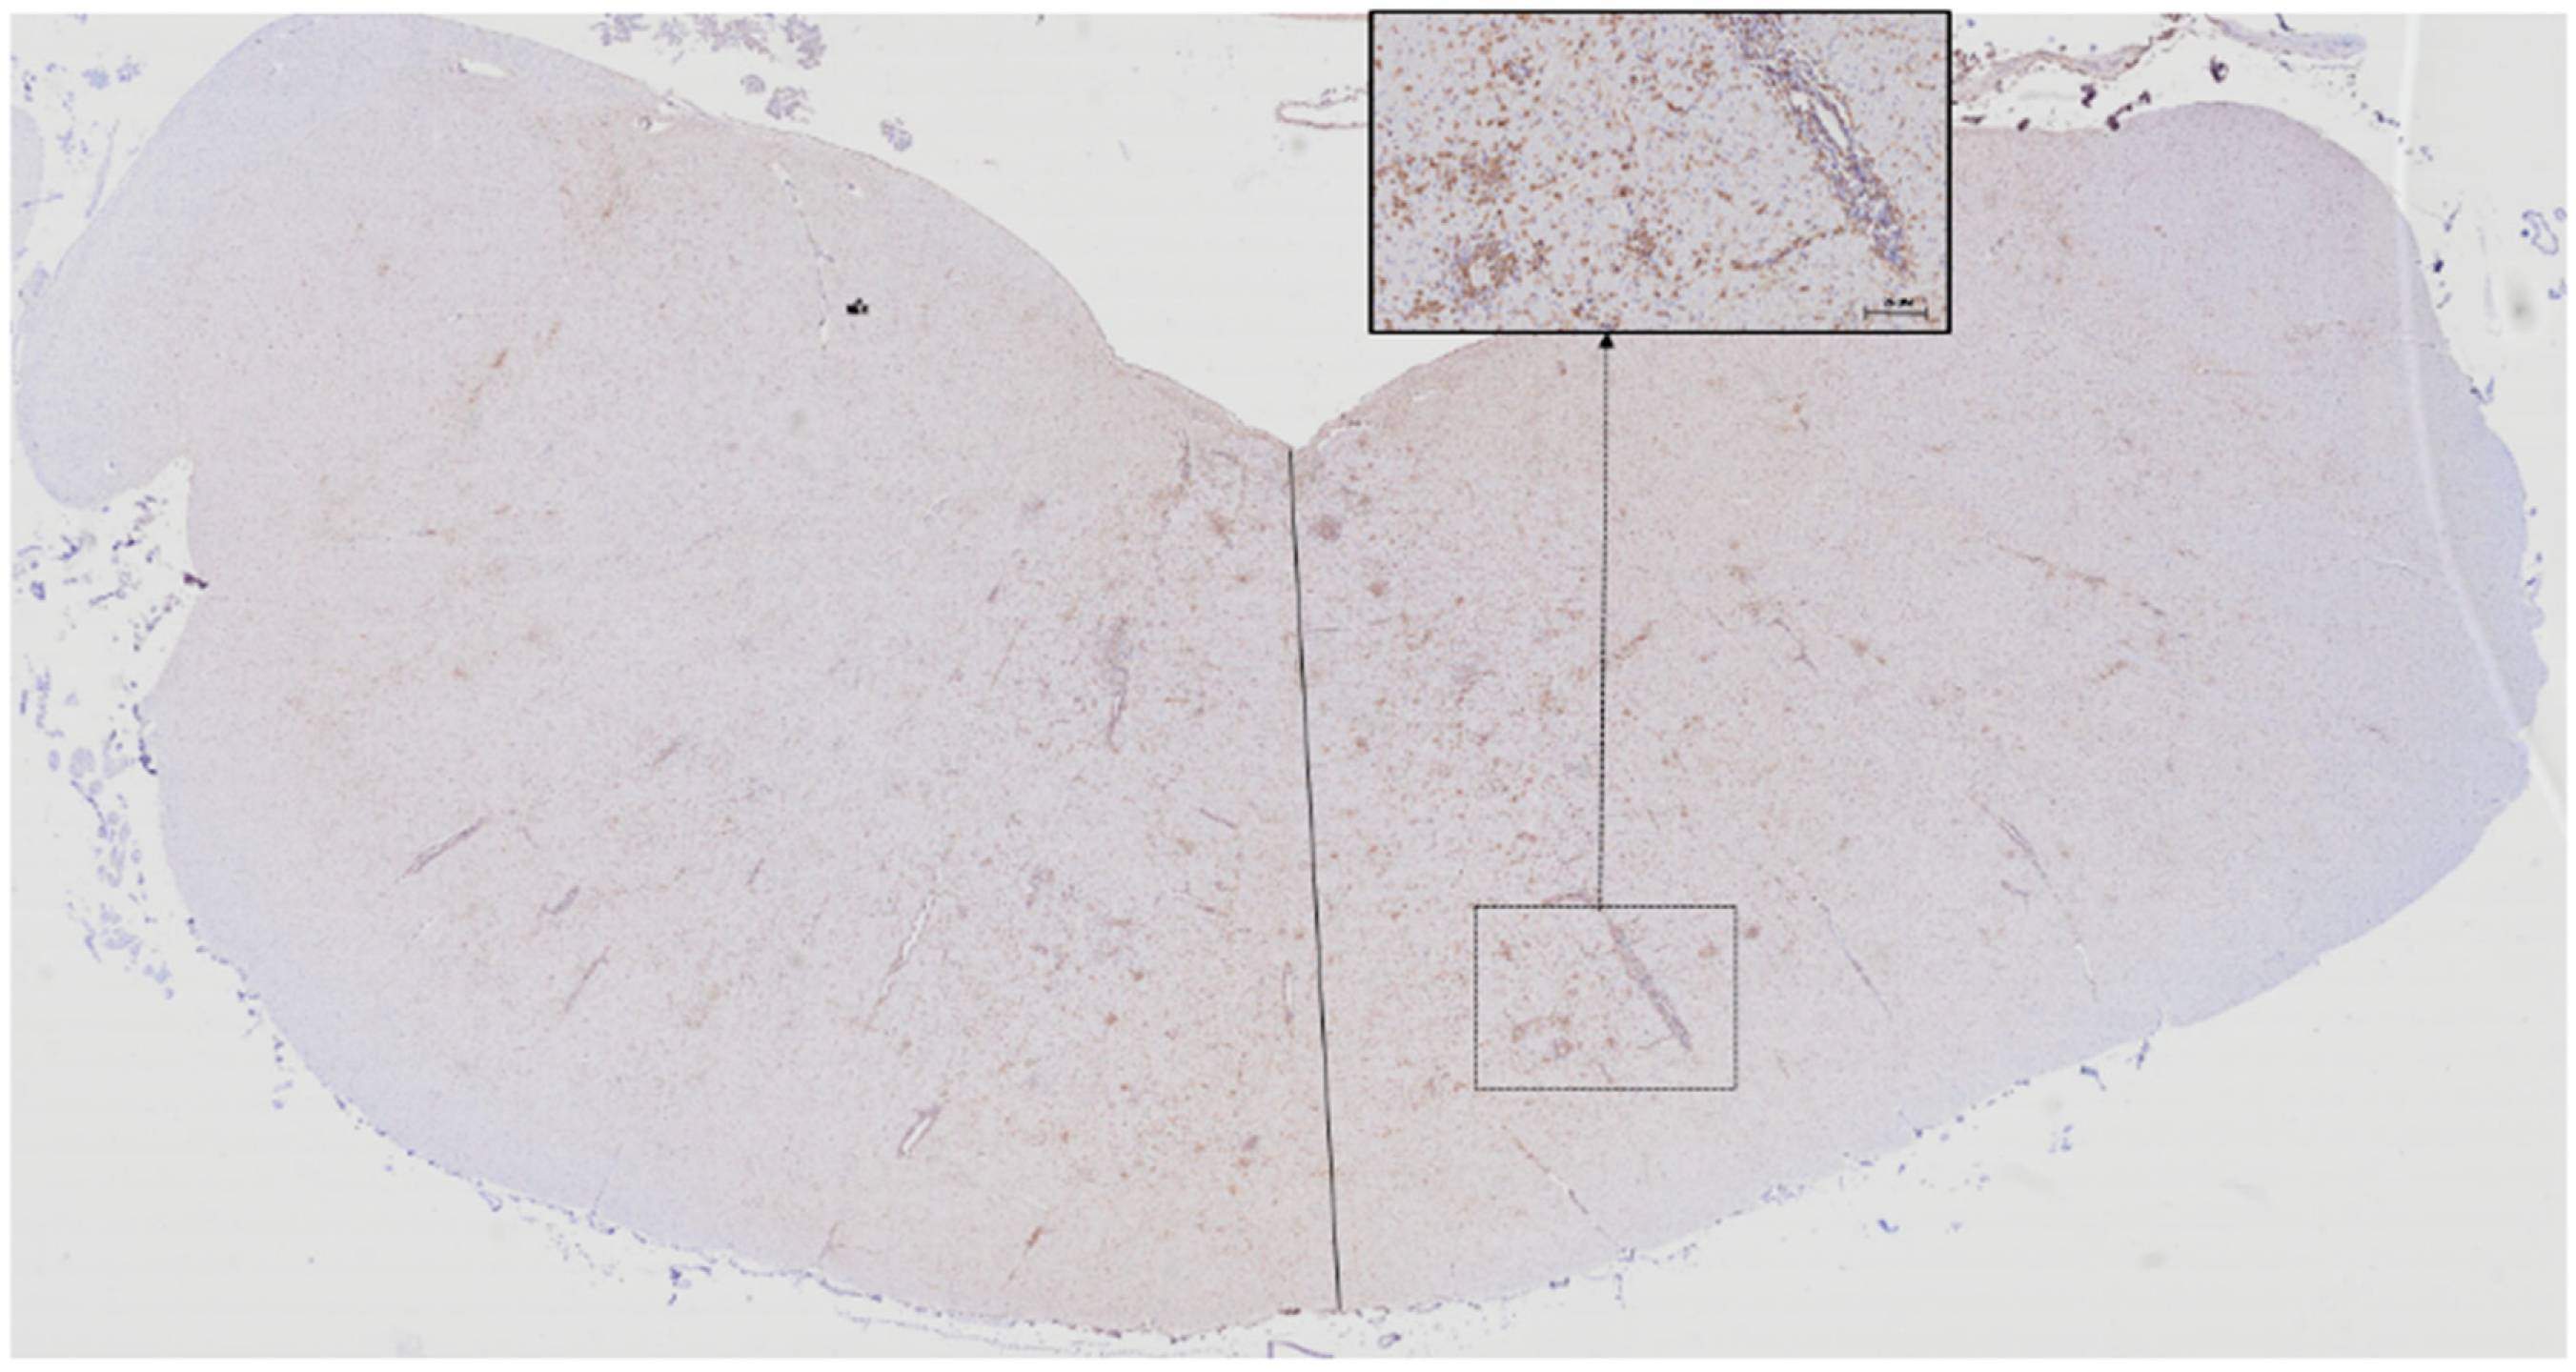

3.1. Microglia

3.2. T lymphocytes

3.3. B lymphocytes

3.4. Proportions of Microglia, T lymphocyte,s and B Lymphocytes According to Lesion Location and Severity